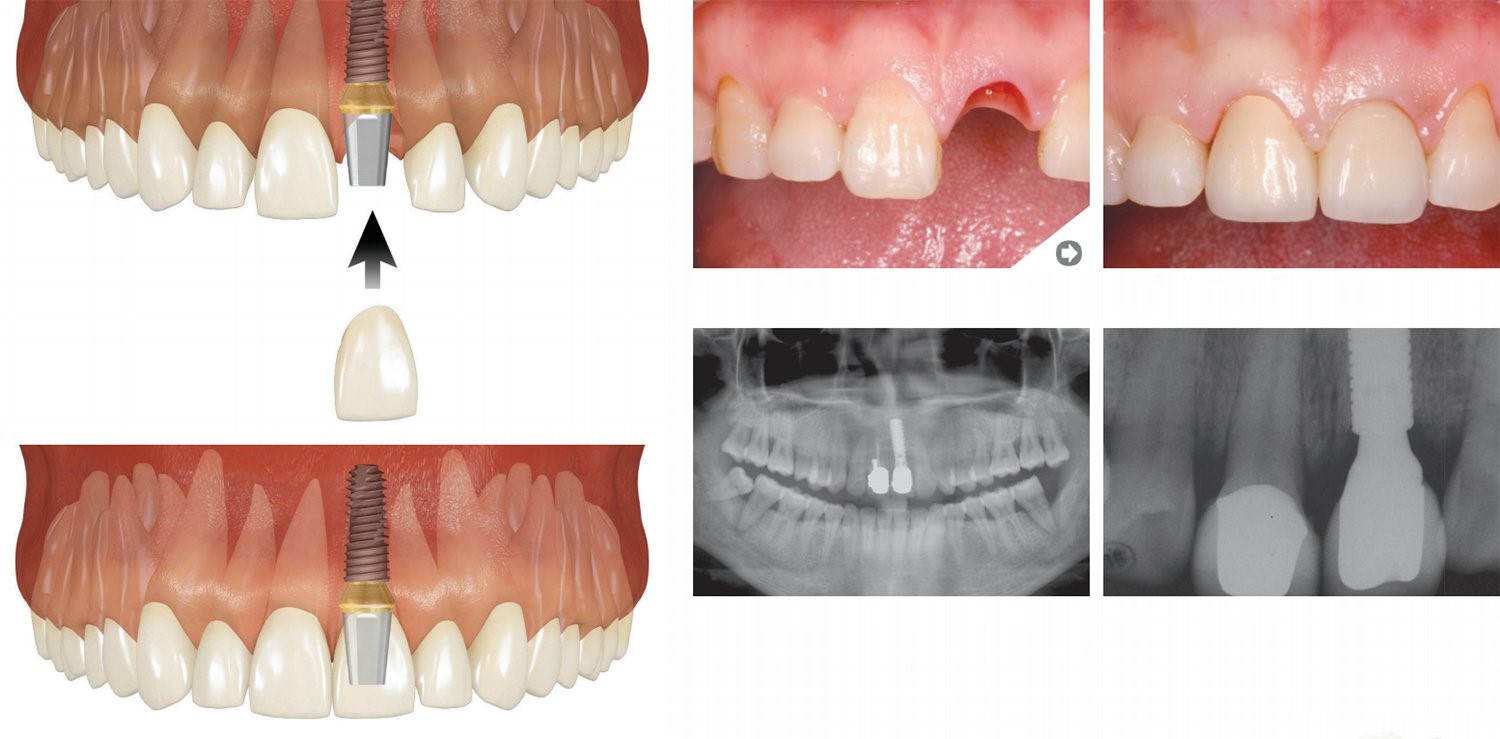

Trūkst viena zoba

Priekšējais zobs